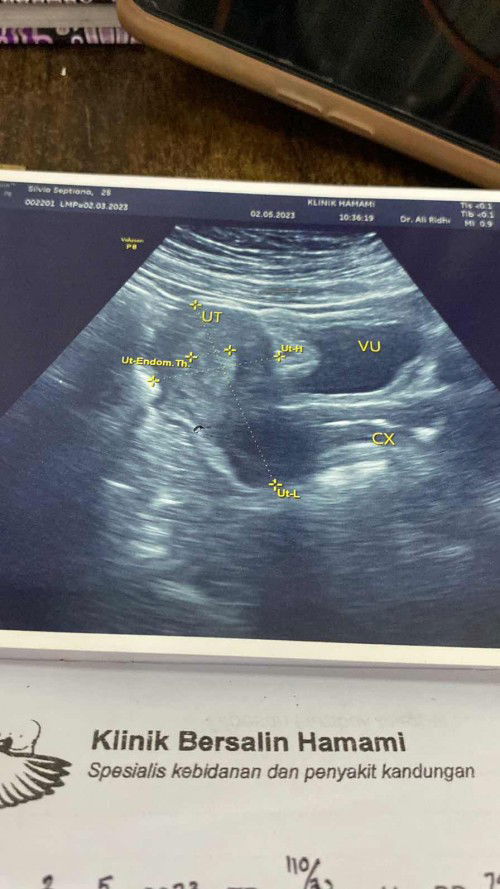

Bun saya udah 2 bln kurang gak haid kmrin tanggal 2 di resepin dokter suruh minum norestil dan kmren saya haid , hariini saya haid ke 2 dan usg transvaginal , dan hasil nya sel tellur saya kecil kecil bun , dikasi dokter obat quenvit itu buat apa yang bunn , tolong yang perna ada sama pengalaman yang aku alamin tolong bantu ceritaain bun sharing #ingintahu #pleasehelp